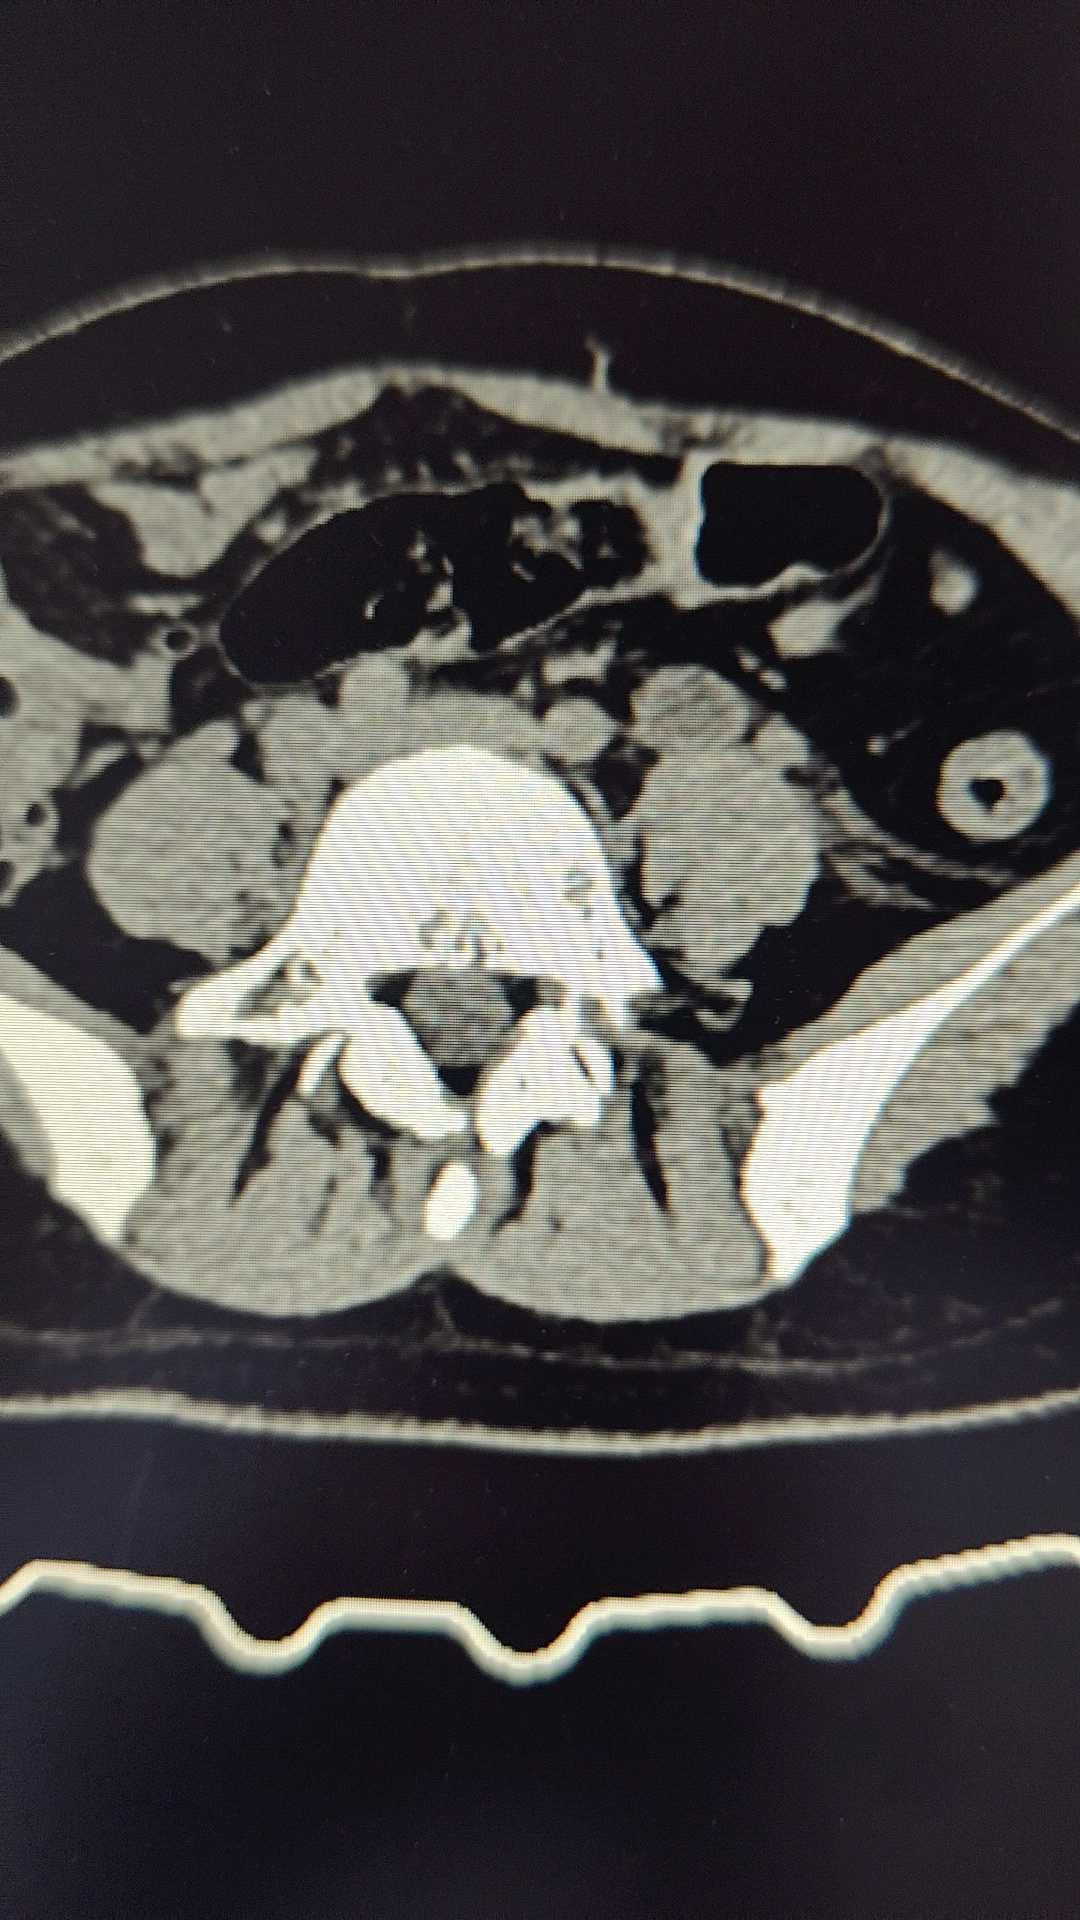

病例女,28岁,发现输尿管结石一年余。

早上一上班,就看到这个夜间来的患者,患者忍耐力确实很强,拟明天手术。

输尿管结石 (165)